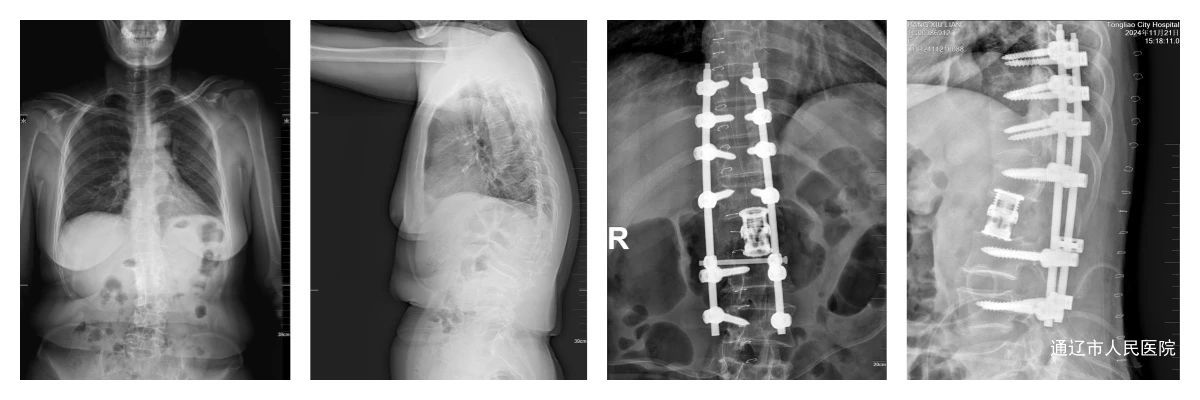

近日,我院脊柱外科团队成功完成一例极具挑战性的胸椎椎板减压及腰1椎体切除人工椎体植入手术,为一位饱受病痛折磨长达20年的患者重新恢复了健康。该术式填补了我市脊柱外科手术的空白。

患者庞某,女,60岁,腰1椎体压缩性骨折病史。多年病症引发胸椎黄韧带钙化等系列并发症,导致右下肢肌力严重受损,仅为1级。日常行走困难,生活无法自理,身心承受巨大痛苦。

面对如此复杂病情,我院脊柱外科房芳主任团队对该病例进行综合研判,评估手术保护脊髓完整性的同时,既要解决胸椎黄韧带钙化对脊髓造成的压迫问题,又要对陈旧性的腰 1 椎体骨折进行妥善处理,就犹如在给生鸡蛋剥壳一样,手术难度和风险极高。与患者及家属商讨后,为其制定了胸椎椎板减压及腰1椎体切除人工椎体植入术的手术方案。

手术在麻醉科等多学科的配合下,由脊柱外科手术团队精准实施。术中,进行胸椎椎板减压,仔细去除钙化的黄韧带,逐步解除脊髓所受的压迫。随后,实施腰1椎体5级截骨,并将人工椎体完美植入,重建脊柱稳定性,手术历时6小时顺利完成。术后患者右下肢肌力逐渐恢复,已提升至2 级,患者极为满意。